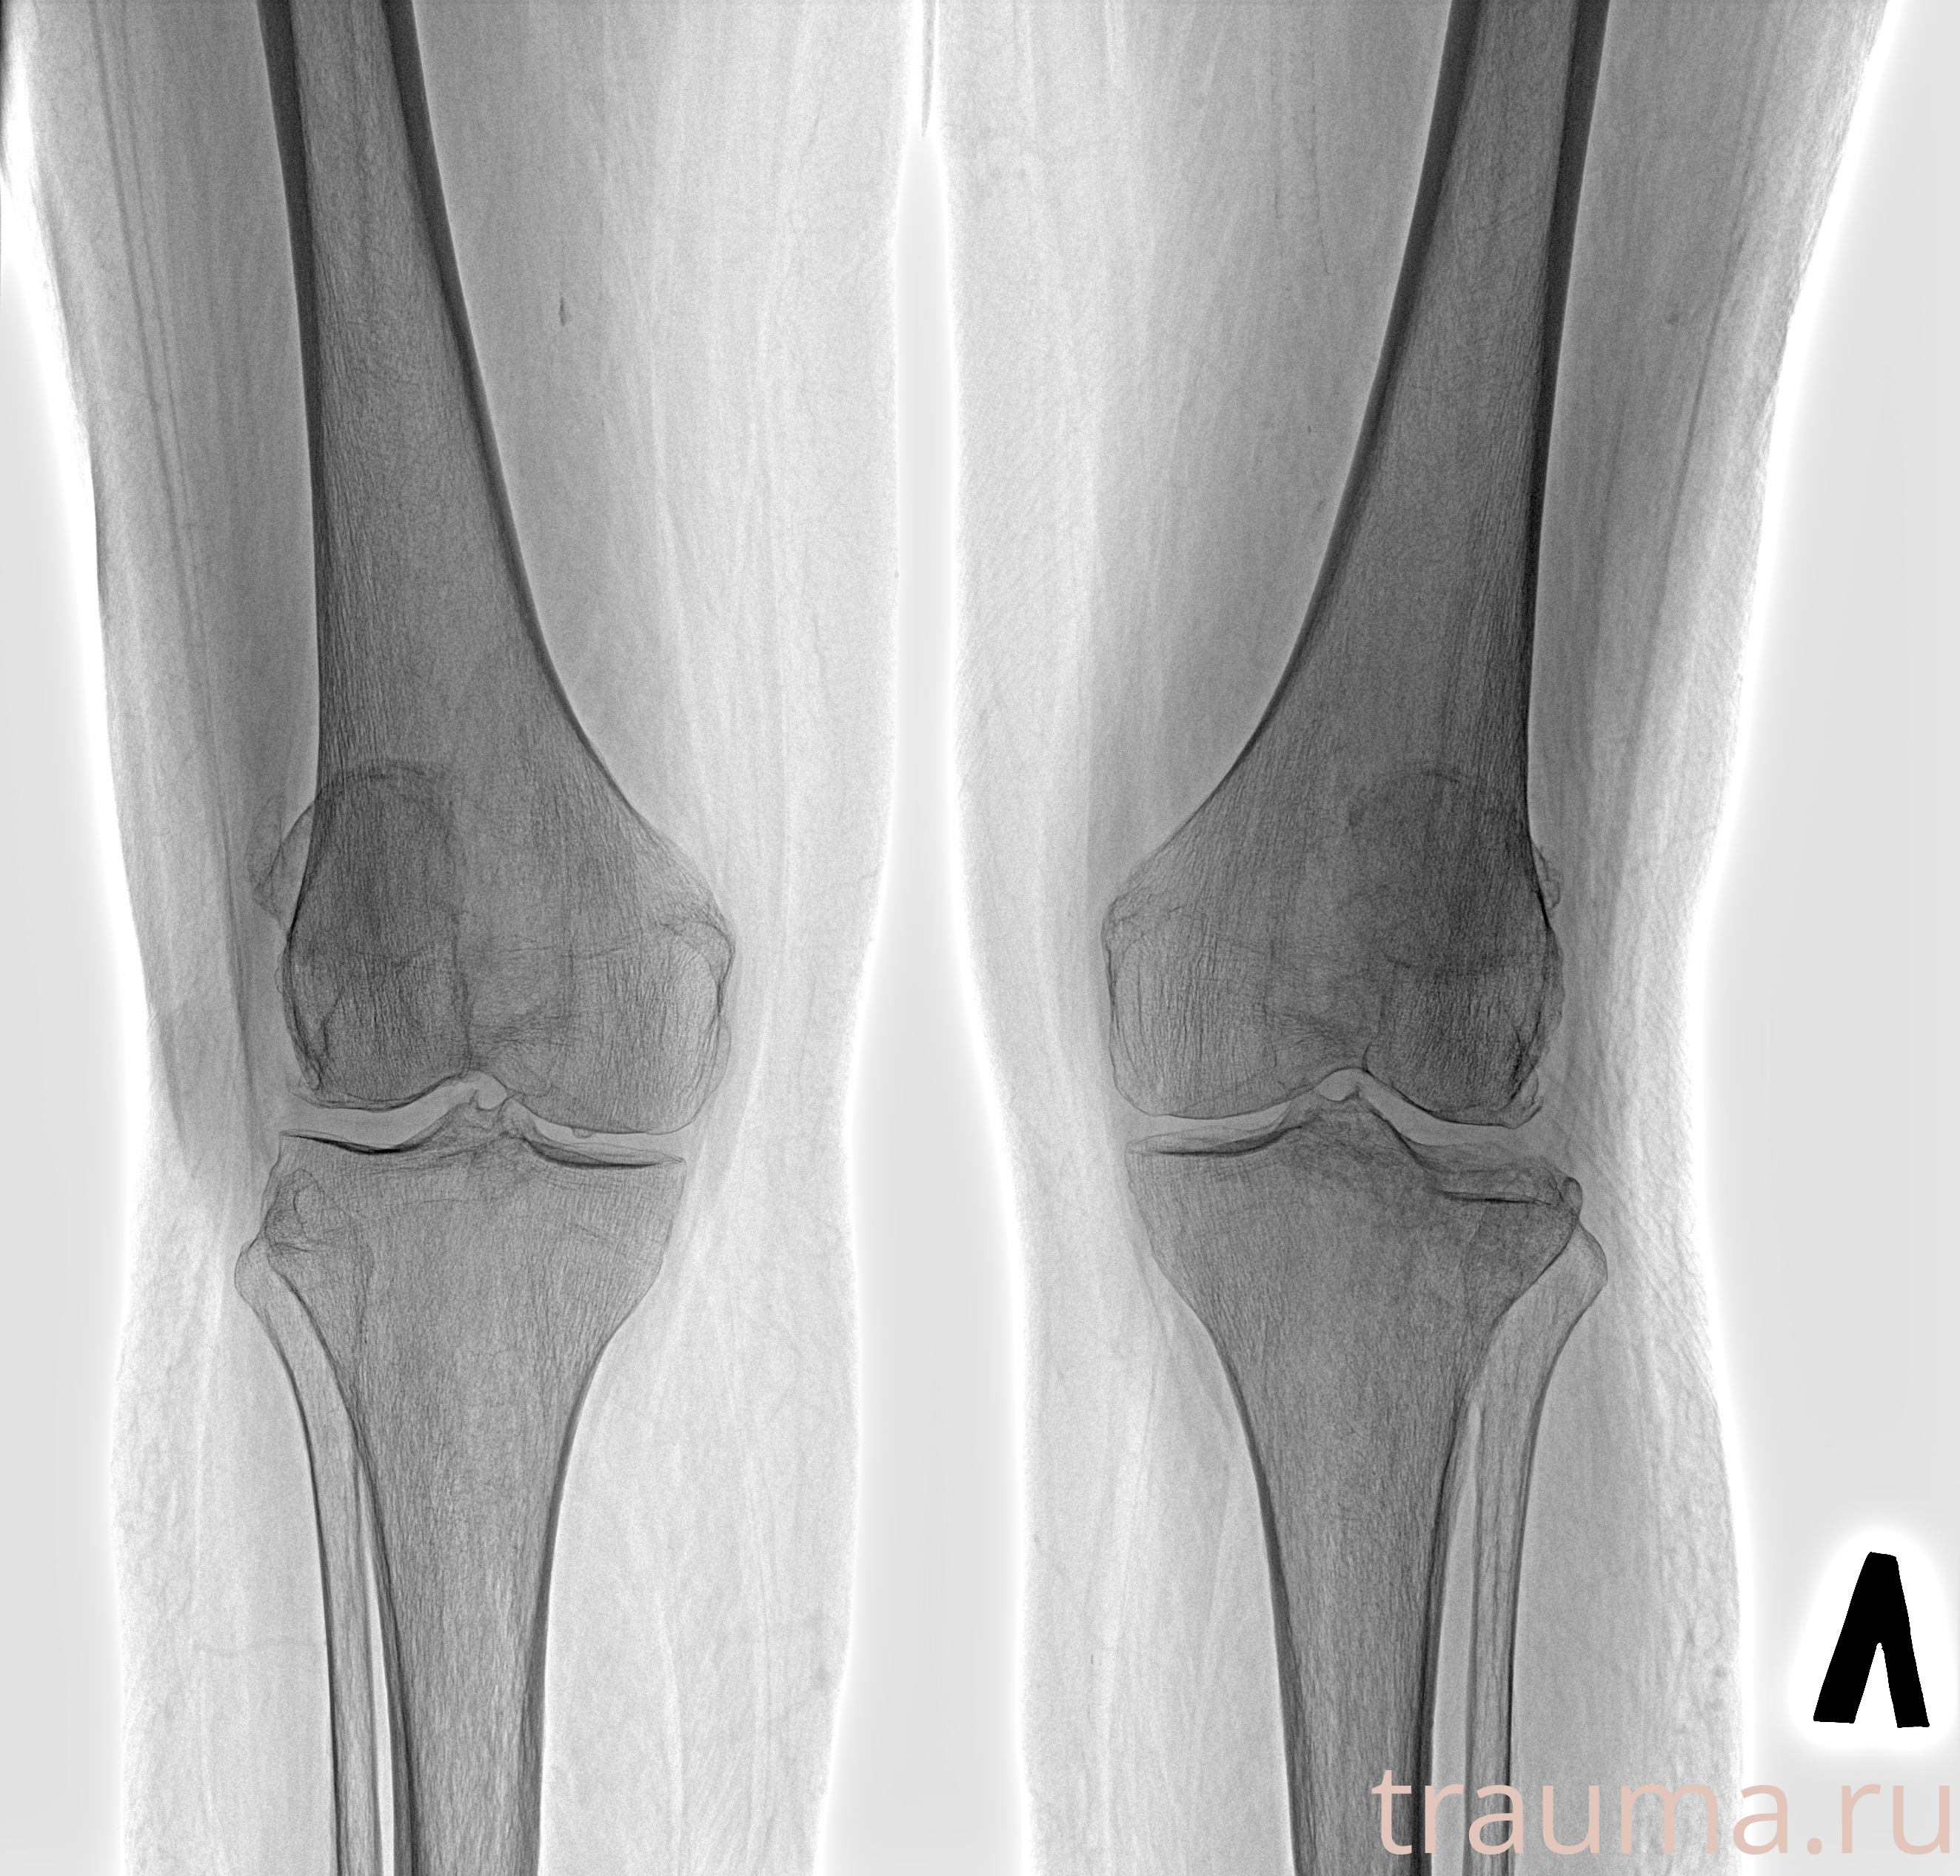

Рентгенограммы

Рентген на дому: по вашему адресу приезжает врач-рентгенолог, травматолог-ортопед с мобильным рентгеновским аппаратом, проводит диагностику травмы или заболевания, делает необходимые рентгенограммы, дает рекомендации по дальнейшему лечению. Получить качественные снимки в домашних условиях возможно благодаря уникальной методике, разработанной МосРентген Центром для института  Склифосовского